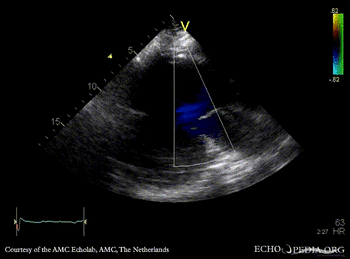

Large pseudoaneurysm of posterior wall

PLAX: large pseudoaneurysm of posterior wall PLAX: Color Doppler, severe mitral regurgitation